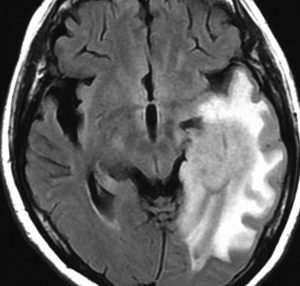

expanding, solid 固形腫瘍的なもの

壊死ではない「のう胞」を伴い,ガドリニウムで強く増強されます。グレード 4 (膠芽腫)と間違えるようなものです。しかし,のう胞はありますが中心壊死がありません。

腫瘍を大部分摘出できるので,積極的な摘出術をして,手術後には放射線化学療法を加えます。この例では,手術後の放射線治療計画の領域が狭ければ,60グレイを使用できる部位です。